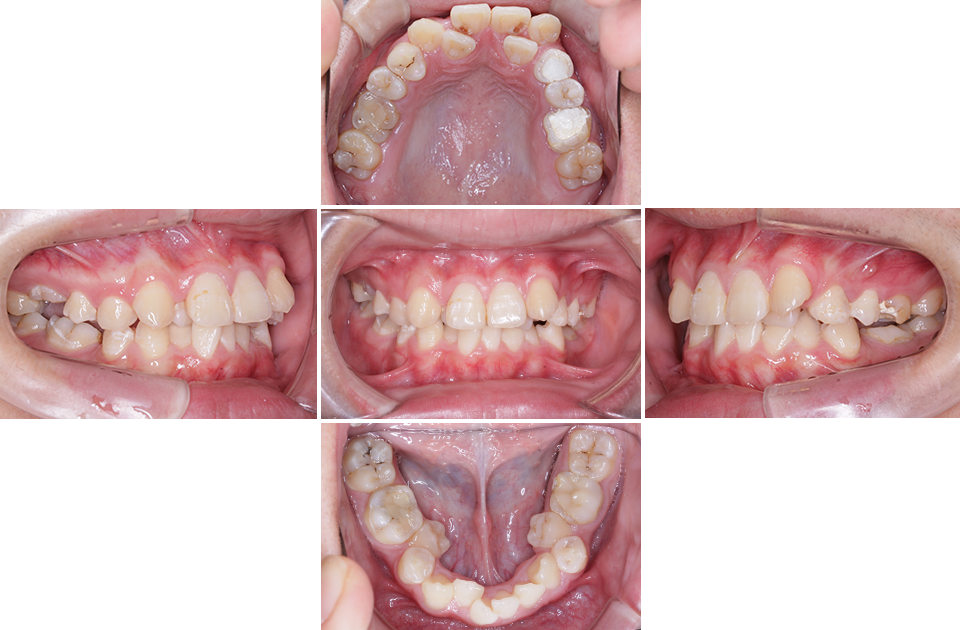

矯正前

矯正前 正面

矯正前 右側

矯正前 左側

矯正前 上顎

矯正前 下顎

主訴 凸凹の歯並びを治したい。虫歯が多い。

年齢 10代男性

治療法 上下顎マルチブラケット装置

抜歯の有無 上顎左右第一大臼歯、上顎左側第一小臼歯、下顎左右側第一大臼歯